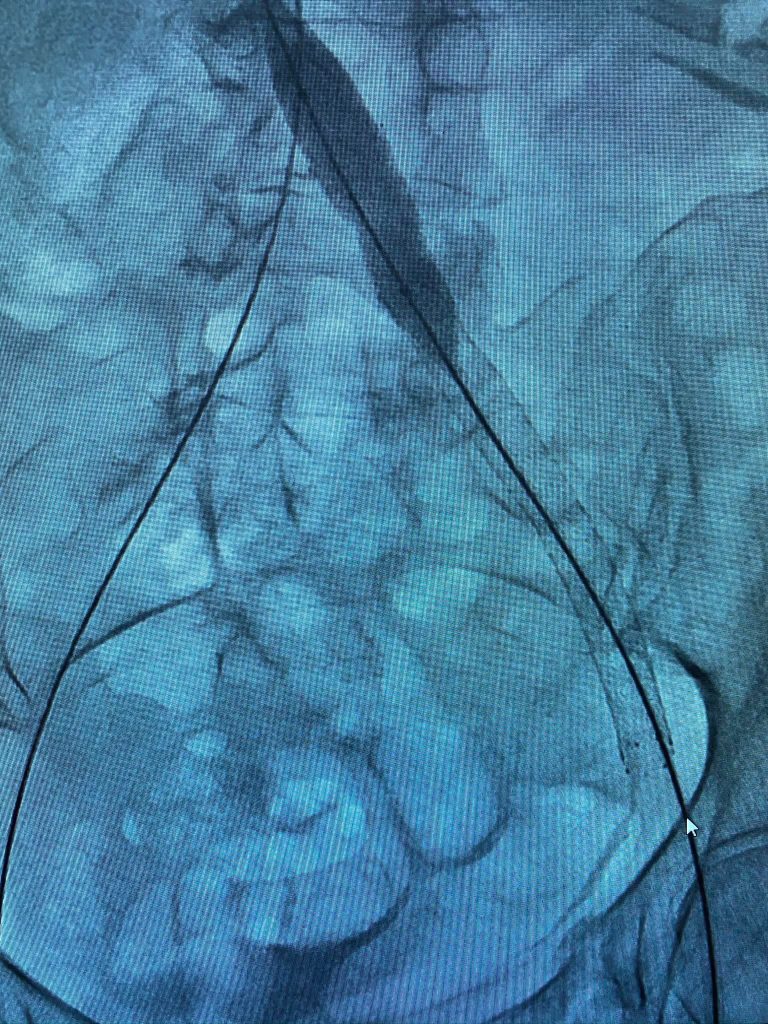

Case of the Day – May-Thurner Syndrome

We present to you a great case of May-Thurner Syndrome also known as Iliac Vein Compression Syndrome. Learn how our team perservered.